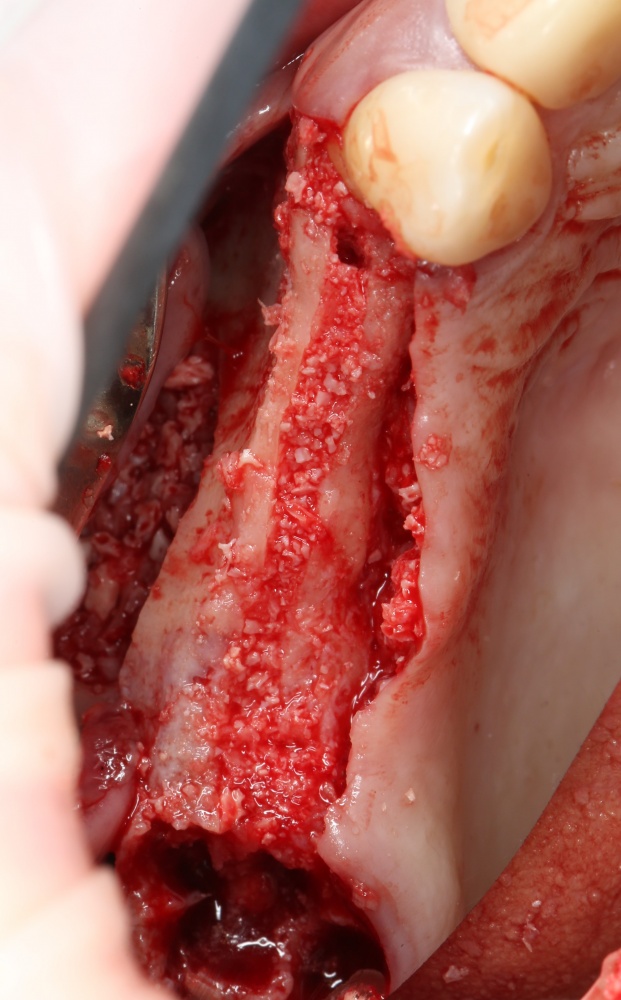

3. Скелетирование альвеолярного гребня.

В отличие от других видов остеопластики, не проводится. Напомню, что для перемещаемого фрагмента, периост является единственным источником питания, и было крайне безответственно лишать кость этого источника. Кроме того, периост частично удерживает перемещаемый фрагмент на месте, не давая ему совсем уж отвалиться.

Максимум, выделите себе полоску шириной в 3-4 миллиметра для работы инструментом и фиксации винтов. Этого будет достаточно.

5. Собственно, расщепление.

Для начала, выкидываем молоток нафиг. Уверен, если вам хоть раз стучали по голове молотком, то вы это уже сделали. Если еще нет, то попробуйте постучать, а потом выкидывайте.

Расщепление можно делать с помощью обычных элеваторов:

не суть. Любые из этих инструментов годятся для нашей работы. И, если честно, мне кажется, что обычные элеваторы гораздо удобнее.

Сдвинув перемещаемый костный фрагмент, вы наверняка с удивлением заметите, что он перемещается назад за счёт ригидности тканей. Поэтому теперь нам нужно подумать, как его удержать.